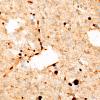

NEOPLASMS (GLIAL)

Astrocytoma, IDH-mutant, WHO Grade 2 (12)